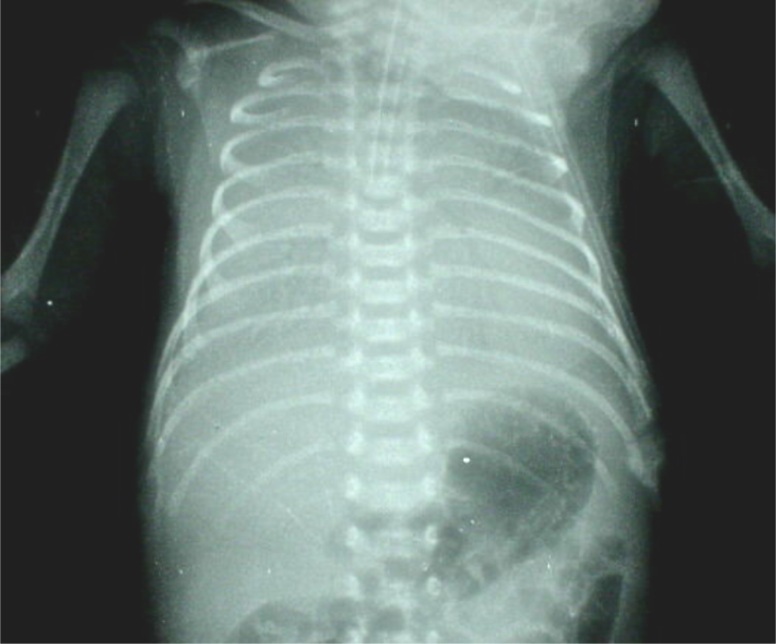

早产儿〔970g〕生后第一天:

“ white lung”(grade IV RDS)